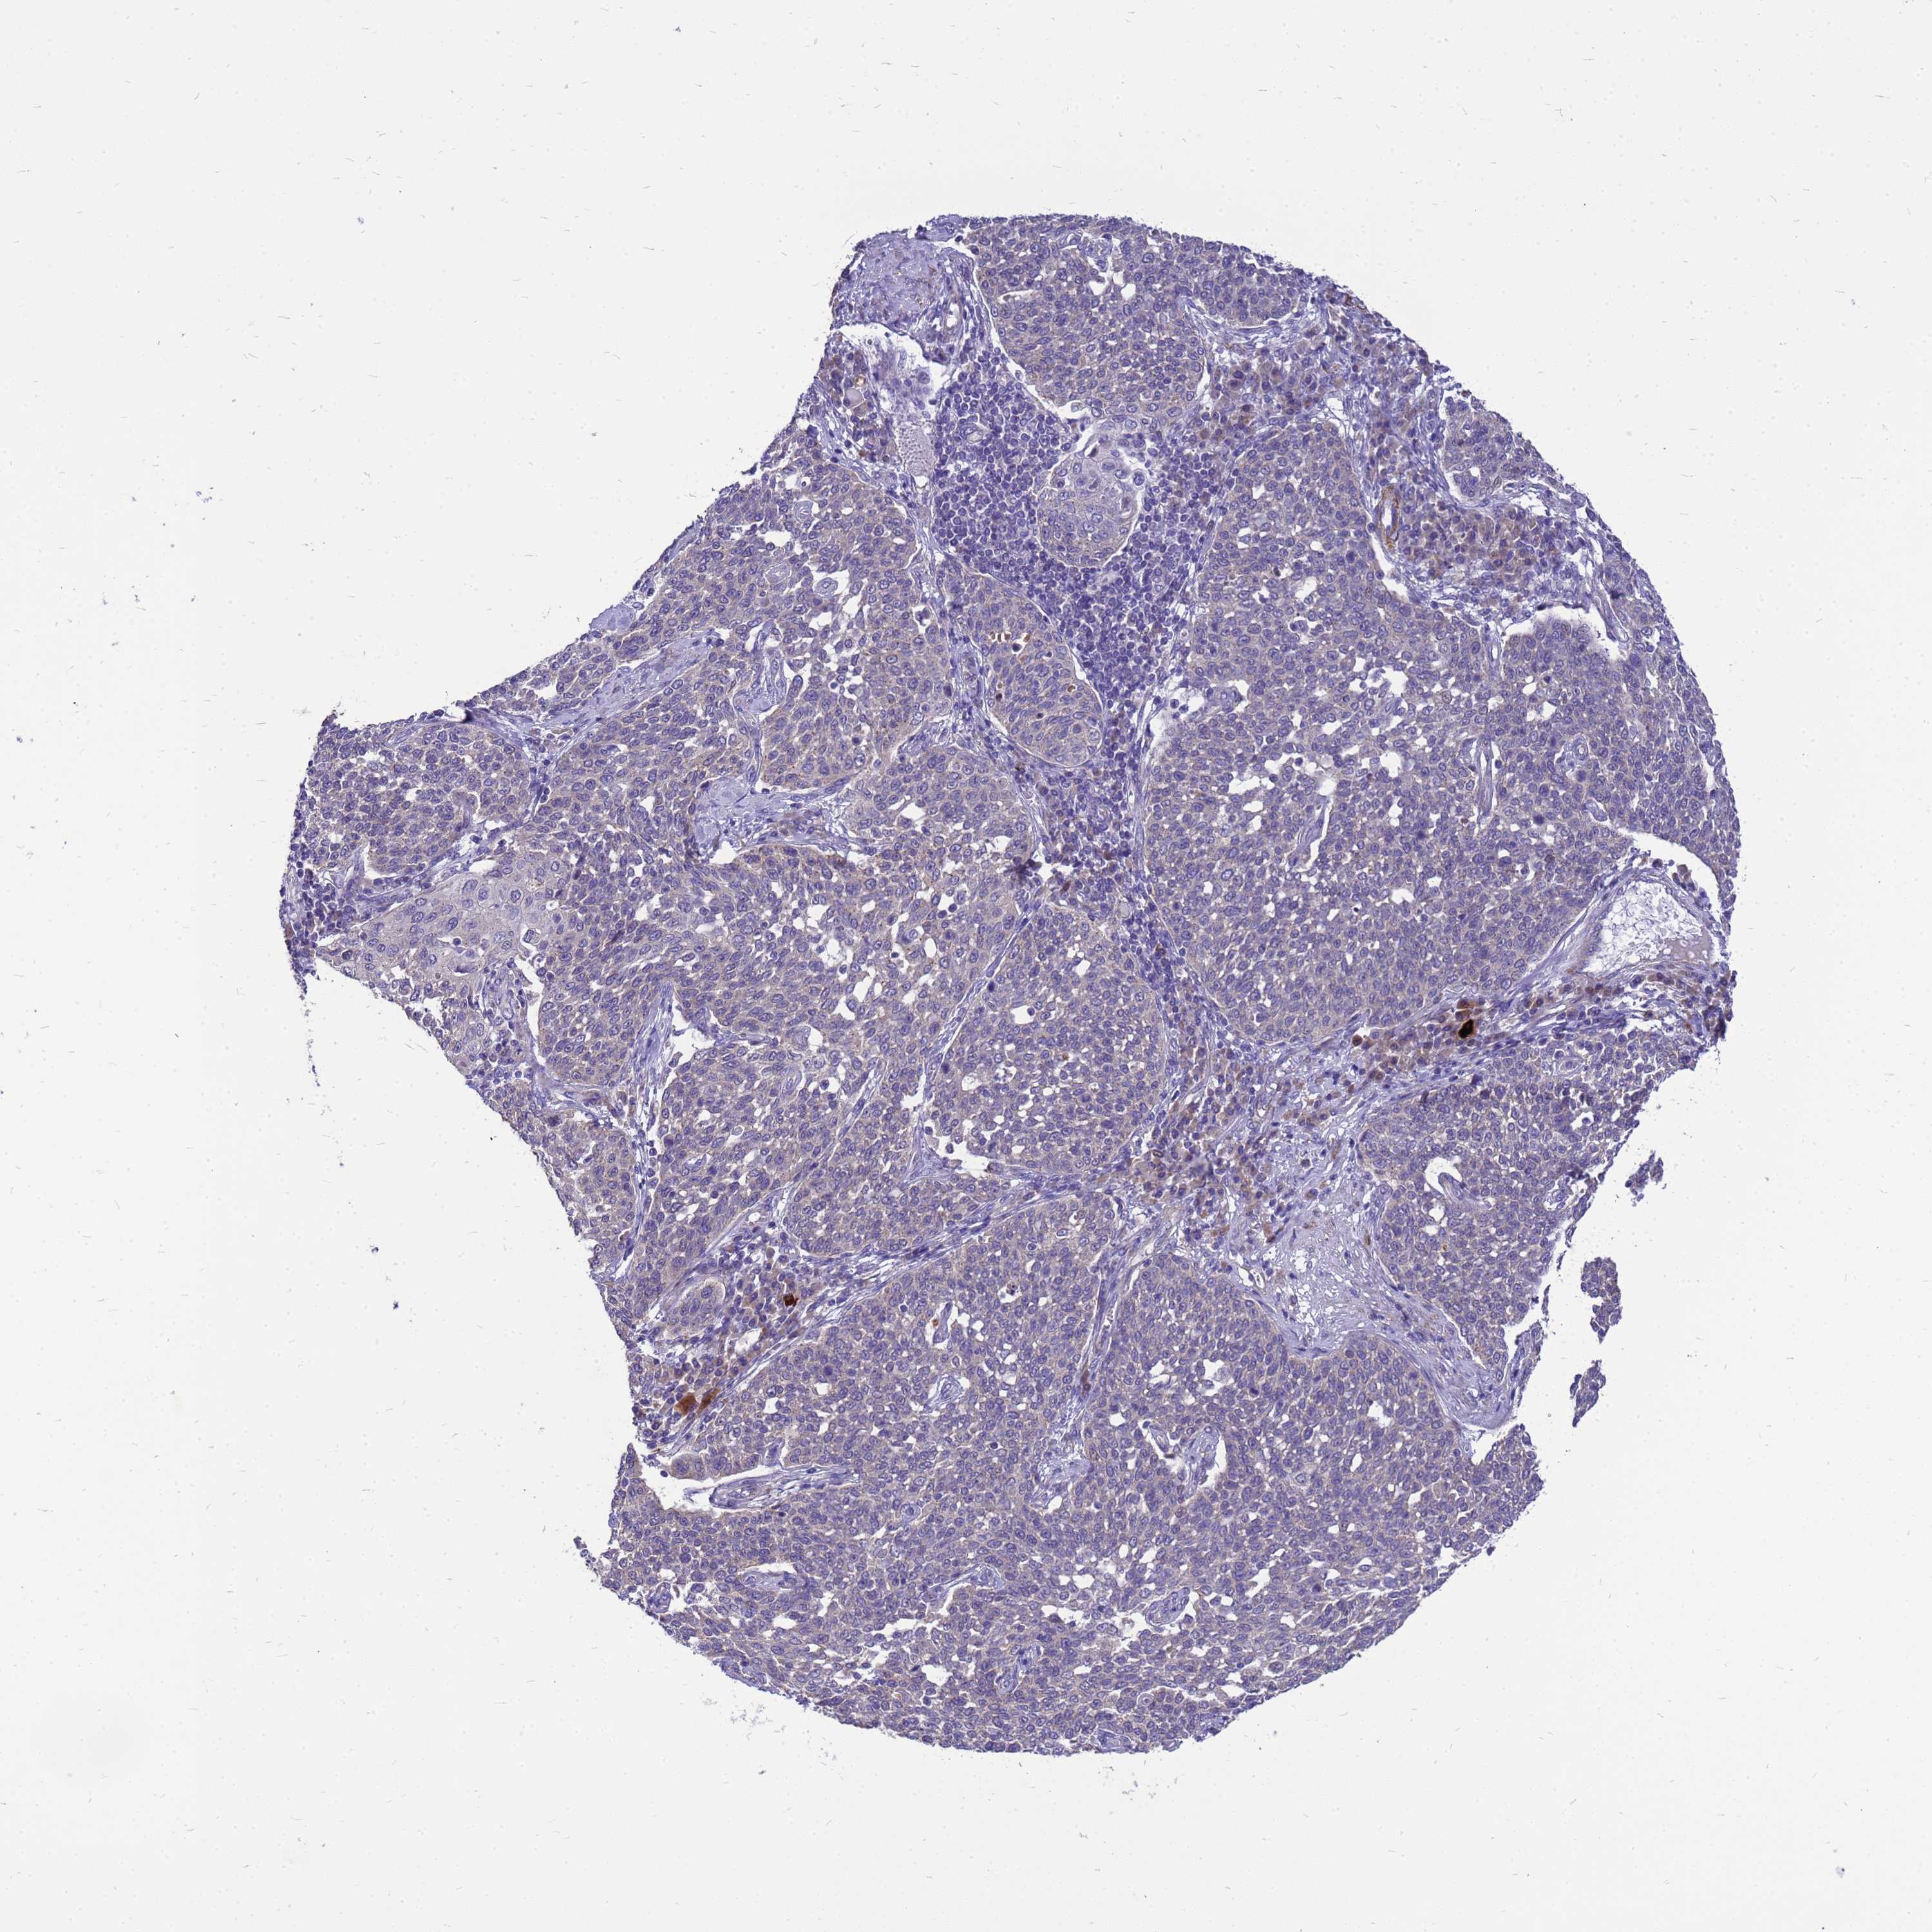

CERVICAL CANCER - Protein expressioni

A mouse-over function shows sample information and annotation data. Click on an image to view it in a full screen mode. Samples can be filtered based on level of antibody staining by selecting one or several of the following categories: high, medium, low and not detected. The assay and annotation is described here.

Note that samples used for immunohistochemistry by the Human Protein Atlas do not correspond to samples in the TCGA dataset.

Antibody stainingi

Antibody staining in the annotated cell types in the current human tissue is reported as not detected, low, medium, or high, based on conventional immunohistochemistry profiling in selected tissues. This score is based on the combination of the staining intensity and fraction of stained cells.

Each image is clickable and will lead to virtual microscopy that enables deeper exploration of all samples and also displays staining intensity scores, fraction scores and subcellular localization as well as patient and tissue information for each sample.

Antibody HPA021007

Staining

High

Medium

Low

Not detected

Intensity

Strong

Moderate

Weak

Negative

Quantity

>75%

75%-25%

<25%

None

Location

Nuclear

Cytoplasmic/membranous

Cytoplasmic/membranous,nuclear

Squamous cell carcinoma, NOS

Adenocarcinoma, NOS